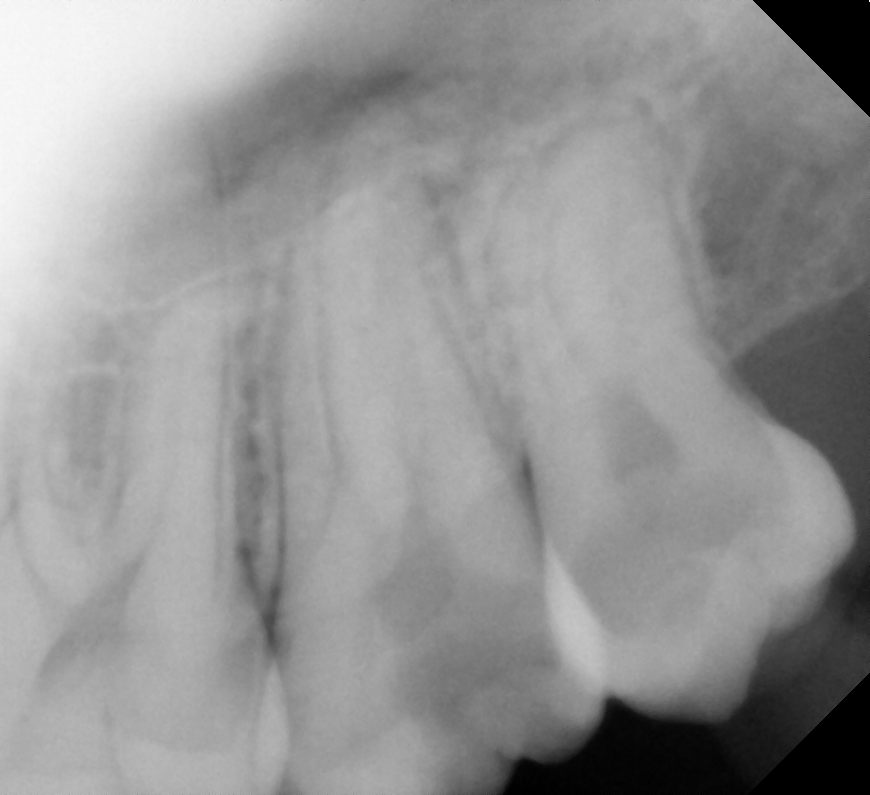

Disto Angular

After After

Before Before